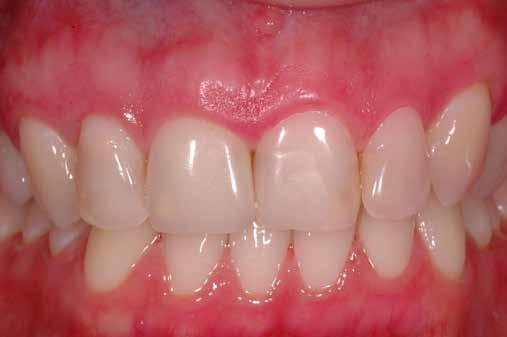

A 2020 januárjában elkezdett kezeléssorozat befejezését az év márciusában, hazánkba is begyűrűző Covid-19 pandémia késleltette, így kb. 6 hónap gyógyulás után láttunk hozzá az emergencia profil és a gingivális zenit ideiglenes koronával történő formázásához (11. és 12. kép). A 3 hetente végzett apró alakításokkal sikerült megfelelő ínyprofilt kialakítani, a „rózsaszín esztétika” a páciens számára is megfelelő volt. A bal felső nagymetsző fog meziális kompozit tömés cseréjét követően, individualizált nyitott kanalas lenyomati fejet készítettünk: az akrilát ideiglenes korona profilját átlátszó szilikonnal lemásoltuk, majd a körszimmetrikus gyári lenyomati fej és az ideiglenes korona kontúrja közötti hézagot folyékony kompozittal töltöttük ki (13. kép). Az így készített egyéni lenyomati fejjel vettünk lenyomatot a végleges, kerámialeplezésű cirkónium-dioxid vázas, átmenő csavaros rögzítésű koronához. (A fogtechnikai munkát Nébl Péter fogtechnikusmester készítette.), (14., 15., 16 és 17. képek).

A kész korona átadásakor a páciens elégedett volt az esztétikával, az azóta eltelt évben rendszeres kontrollokon jelent meg, melyek során meggyőződtünk a kemény- és lágyszövetek stabilitásáról (18. és 19. képek).

17. a–b képek: A kész munka átadáskor. 18. a–c képek: 1 éves kontroll. 19. kép: Intraorális kontroll röntgen felvétele 1 évvel az átadás után.